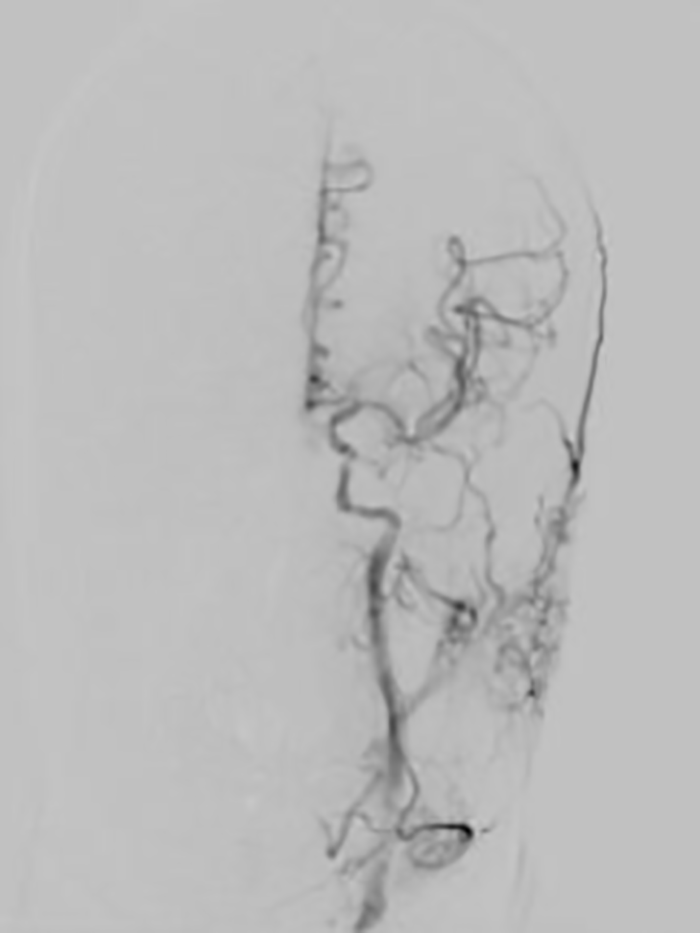

作为配合多年的老搭档,神经内科介入团队陈金龙主任医师、卢红腾主治医师与鲁红梅护士精细操作、密切协作,有条不紊地实施左侧颈内动脉窦部次全闭塞再通术(球囊扩张、支架置入)及左侧大脑中动脉取栓术。

经过两个小时的抢救,患者血管全部再通,手术取得成功!

▲患者术后脑血管完全再通